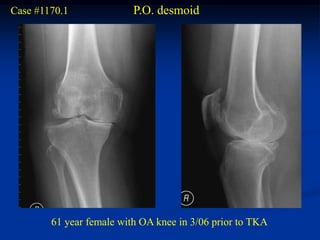

Case #1170.1              P.O. desmoid

61 year female with OA knee in 3/06 prior to TKA

Sag MRI 4/03

T-1                  T-2

MRI 1 year PO TKA

Sag T-2                       Gad

Axial

Gad

Surgical resection